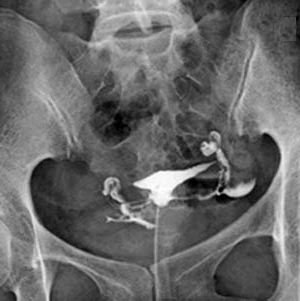

こちらの画像は、女性の生殖器をコントロールする自律神経の支配図です。

妊娠に直接関係する卵巣、卵管、子宮、膣の働きをコントロールする自律神経が、背骨の上部(第5胸椎)から骨盤(仙骨5番)までの間から卵巣、卵管、子宮、膣につながっています。

わかりやすい画像で説明すると、こんなイメージです。

卵巣、卵管、子宮、膣の働きをコントロールする自律神経が、背中の上部から骨盤から伸びており、赤色の部分が正しい姿勢でない場合は、自律神経の流れが阻害されるので、卵巣、卵管、子宮、膣の働きが悪くなり、妊娠力がとても低くなります。

椅子、ソファー、床に座った時に、骨盤が後ろに倒れ、背骨が後弯(後ろに曲げられる状態)する「妊娠できにくい姿勢」になることで、卵巣、卵管、子宮、膣の働きをコントロールする自律神経(胸椎5番〜仙骨5番)の流れが阻害され卵巣、卵管、子宮、膣の機能が低下してしまい、結果として妊娠力が低下してしまうのです。

更に、骨盤の後傾、背中が丸くなることで、内臓が圧迫され、卵巣、卵管、子宮も圧迫され強いストレスを受けることでその機能が低下して妊娠できにくくなります。

あなたも卵管造影された子宮、卵巣、卵管が傾き捻じれていませんでしたか?